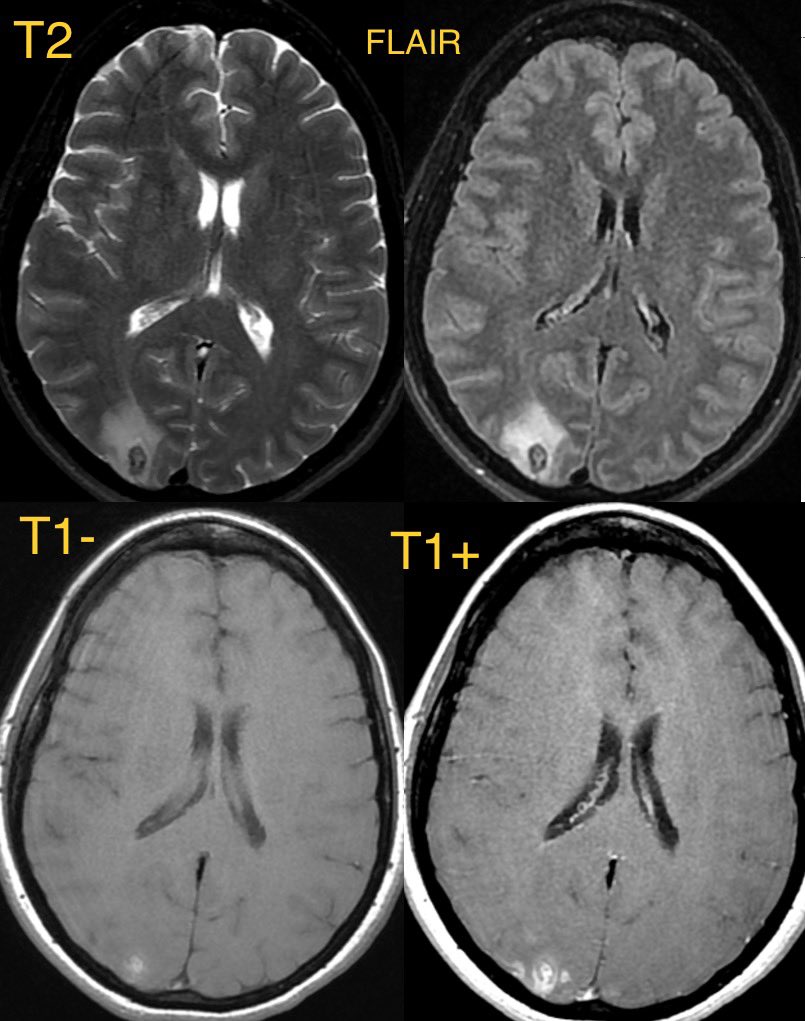

Initial MR shows cortical/subcortical restricted diffusion and edema predominantly in the right Occipital lobe

▶️convexity SAH, lobar hemorrhage, edema, and infarcts

💡 On imaging, MR with VESSEL WALL IMAGING can help to differentiate RCVS from vasculitis which displays much more enhancement while RCVS typically shows little to no enhancement

💡 PRES also has a lot of overlap with RCVS and they can be associated with each other

PRES usually has more edema, more often bilateral, and less often has restricted diffusion and hemorrhage (though it can)